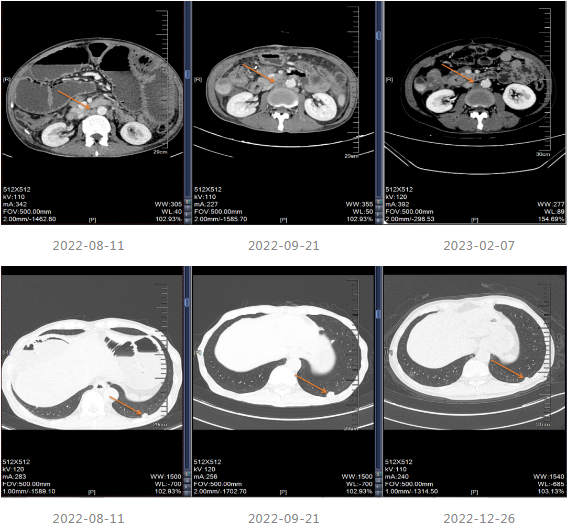

局部治疗:2020-09-26复查MRI提示部分病灶较前缩小,部分增大,于2020-10-22至武汉同济医院行“肝脏病灶微波消融术”,后继续口服卡培他滨至2021-5。

2021.06-01复查影像学提示肝胃间隙及腹膜后淋巴结较前增大,疗效评价PD。

2021-12-15影像学复查提示疾病进展。

2022-04至2022-07采用“贝伐珠单抗联合卡培他滨”维持治疗4周期,维持治疗期间患者渐感腹胀伴消瘦。

202-08出现肠梗阻,内科治疗效果不佳。

患者出现肠梗阻,考虑病情PD,因此2022-10-06至今采用“斯鲁利单抗(200mg q3w)+呋喹替尼(4mg/d,口服,服3周停1周)”进行治疗,治疗过程中患者一般情况良好,体重增加。

该例结肠癌患者治疗进程较长,2019年3月确诊升结肠癌并伴随多发肝转移(三野MSS型)。患者一线采用FOLFIRI联合西妥昔单抗治疗11个周期,疗效评估达到PR,后续采用卡培他滨维持治疗,并于2020年10月进行肝脏病灶微波消融;2021年6月影像学提示疾病进展进入二线治疗,采用贝伐珠单抗联合卡培他滨治疗8个周期后出现疾病进展,换用化疗方案FOLFOX6继续进行治疗6个周期,后续采用贝伐珠单抗联合卡培他滨进行维持治疗,在维持治疗期间出现肠梗阻,考虑疾病进展,且于2022年8月29日进行小肠造瘘术并进入四线治疗,从2022年10月采用斯鲁利单抗联合呋喹替尼进行治疗至今,PFS超过6个月,患者OS大于49个月。该病例提示对于后线MSS型mCRC患者,斯鲁利单抗联合抗血管生成药物可以为患者带来一定的生存获益。